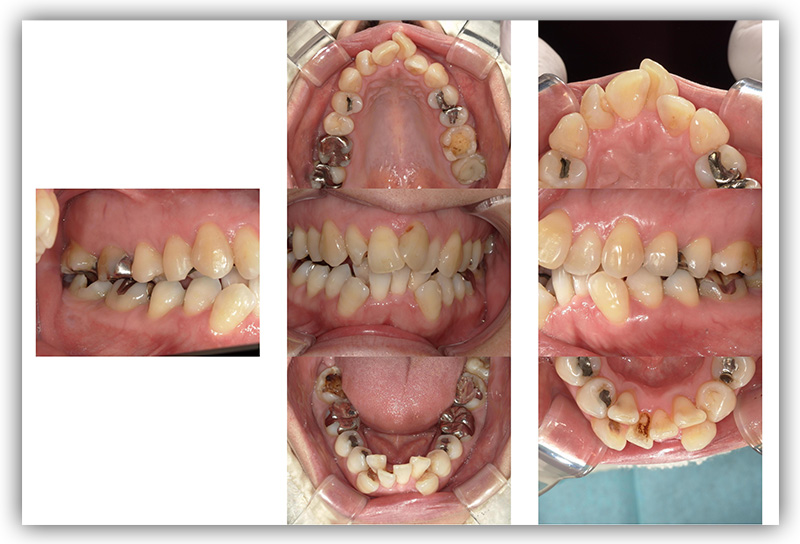

CASE_02

30代女性(インビザライン矯正)

- 患者さん情報(年齢・性別)

- 30代 女性

- 主訴

- 歯並びが気になる。自身の矯正について知りたい。

- 治療箇所

- 1箇所

- 治療方法

- インビザライン

- 費用

- 66万円

- 治療期間

- 1年4か月

- その治療によるリスク・副作用

- 歯肉退縮することがある

- 矯正中はしみたり、痛みを伴うことがある